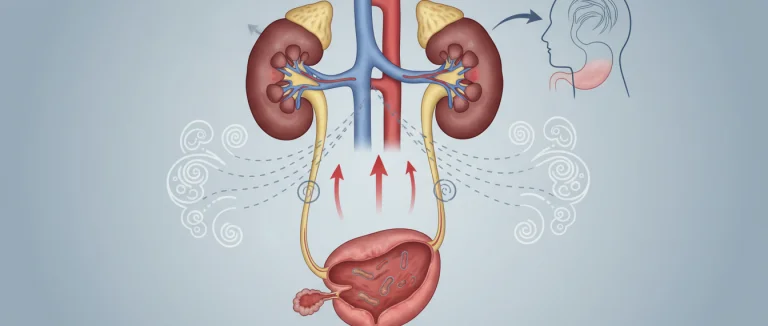

повышенное мочеиспускание

поддержка мочевого пузыря

подтекание мочи

постоянное желание мочиться

почему я так часто мочусь

препараты для контроля мочевого пузыря

простата

Простата

простатическая уретра

Простатa

протекание мочи

протекающий мочевой пузырь